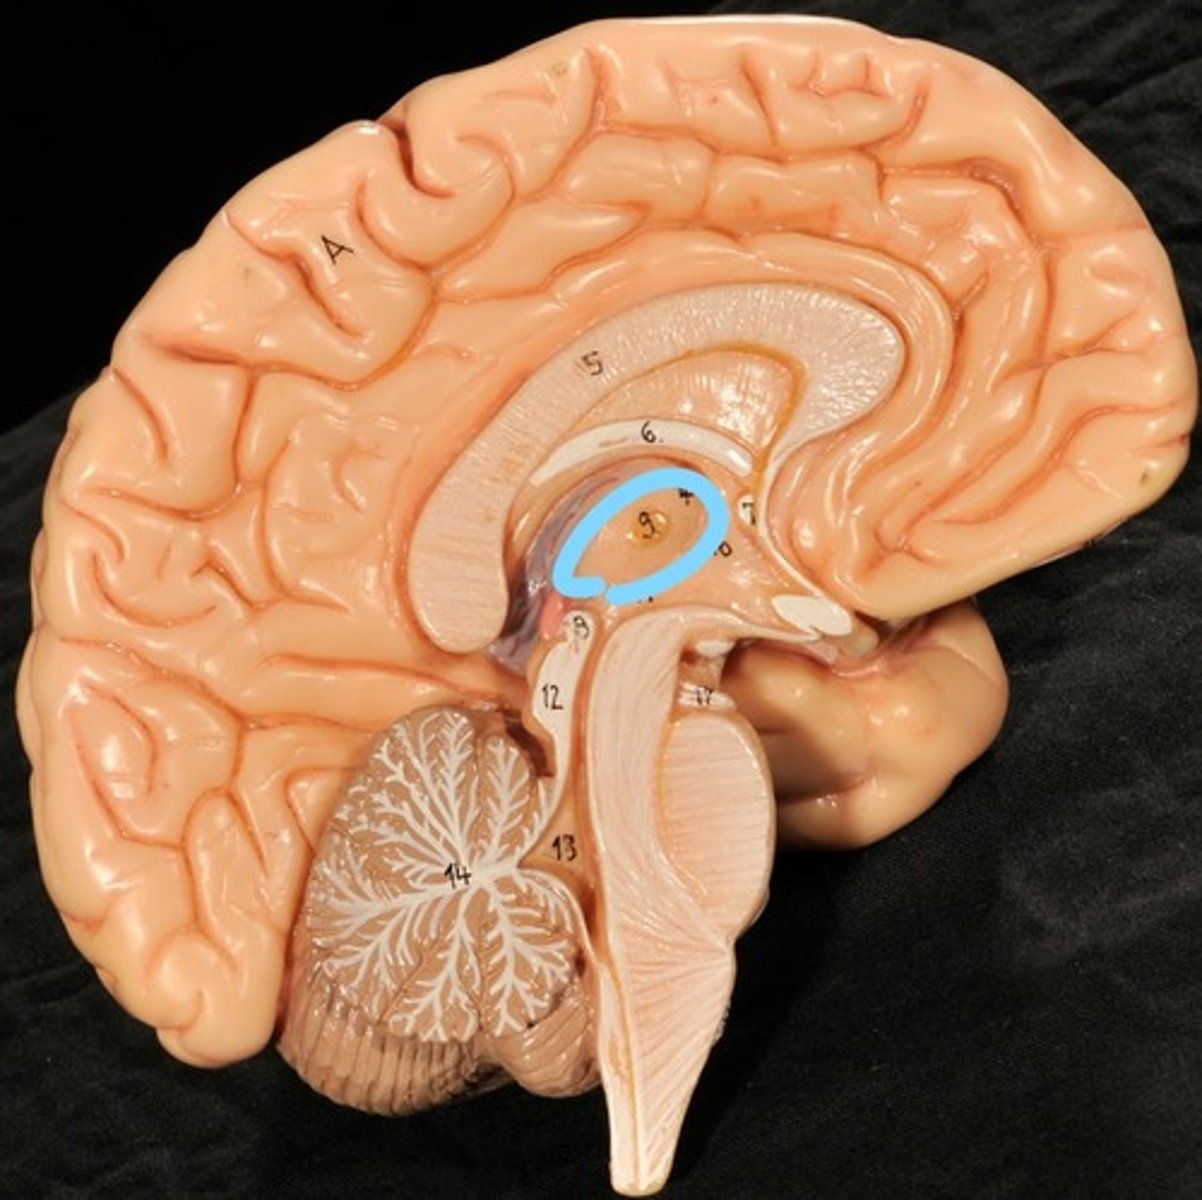

Identify structures of midsagittal brain

Corpus callosum

Diencephalon

thalamus, third ventricle, hypothalamus, epithalamus

Thalamus

Third Ventricle

Hypothalamus

Epithalamus (pink line)

Brain stem

Pons

Medulla oblongata

choroid plexus of third ventricle

produces cerebrospinal fluid

Third ventricle

cerebral aqueduct (midbrain)

midbrain

Fourth ventricle

Central Canal of brain

Takes Cerebrospinal fluid down to the spinal cord

Thalamus